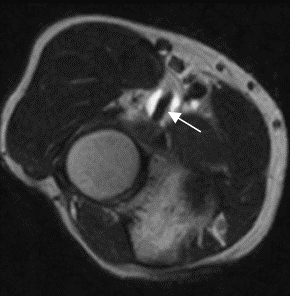

Fig 52 B. Bursitis del bíceps.

RM axial en T2. Líquido rodeando completamente la inserción del tendón del bíceps braquial, por bursitis.